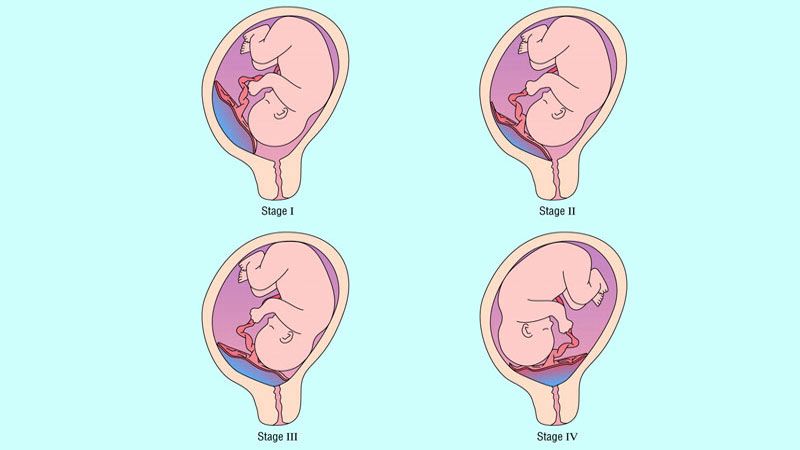

- Prezentasyon anomalileri (Bebeğin rahim içinde duruş problemleri)

Normalde bir fetus rahim içinde en sık olarak “baş aşağı pozisyonda” durur. Ancak plasenta previada doğum kanalının önünü plesenta kapattığı için bebek; makat aşağı, transvers (yan), oblik (çapraz) şekillerde durabilir. Plasenta previa olgularının %30’unda makat geliş ya da yan geliş durumu bulunması da bebeğin içinde bulunduğu riski arttırır.